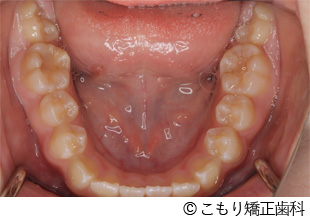

【症例1】上顎小臼歯抜歯によるガタガタの改善

- 上顎小臼歯抜歯によるガタガタの改善

- 924,000円(税込)

- 治療費 880,000円、検査料44,000円

- 2年11ヵ月

- 12歳女性

叢生(ガタガタ)、交叉咬合。

上下顎マルチブラケット装置(上顎両側第一小臼歯抜歯)を用いて叢生の改善を行った。

年齢が若いため、今後の下顎の成長をふまえた咬合関係を構築することで長期安定性を高めています。